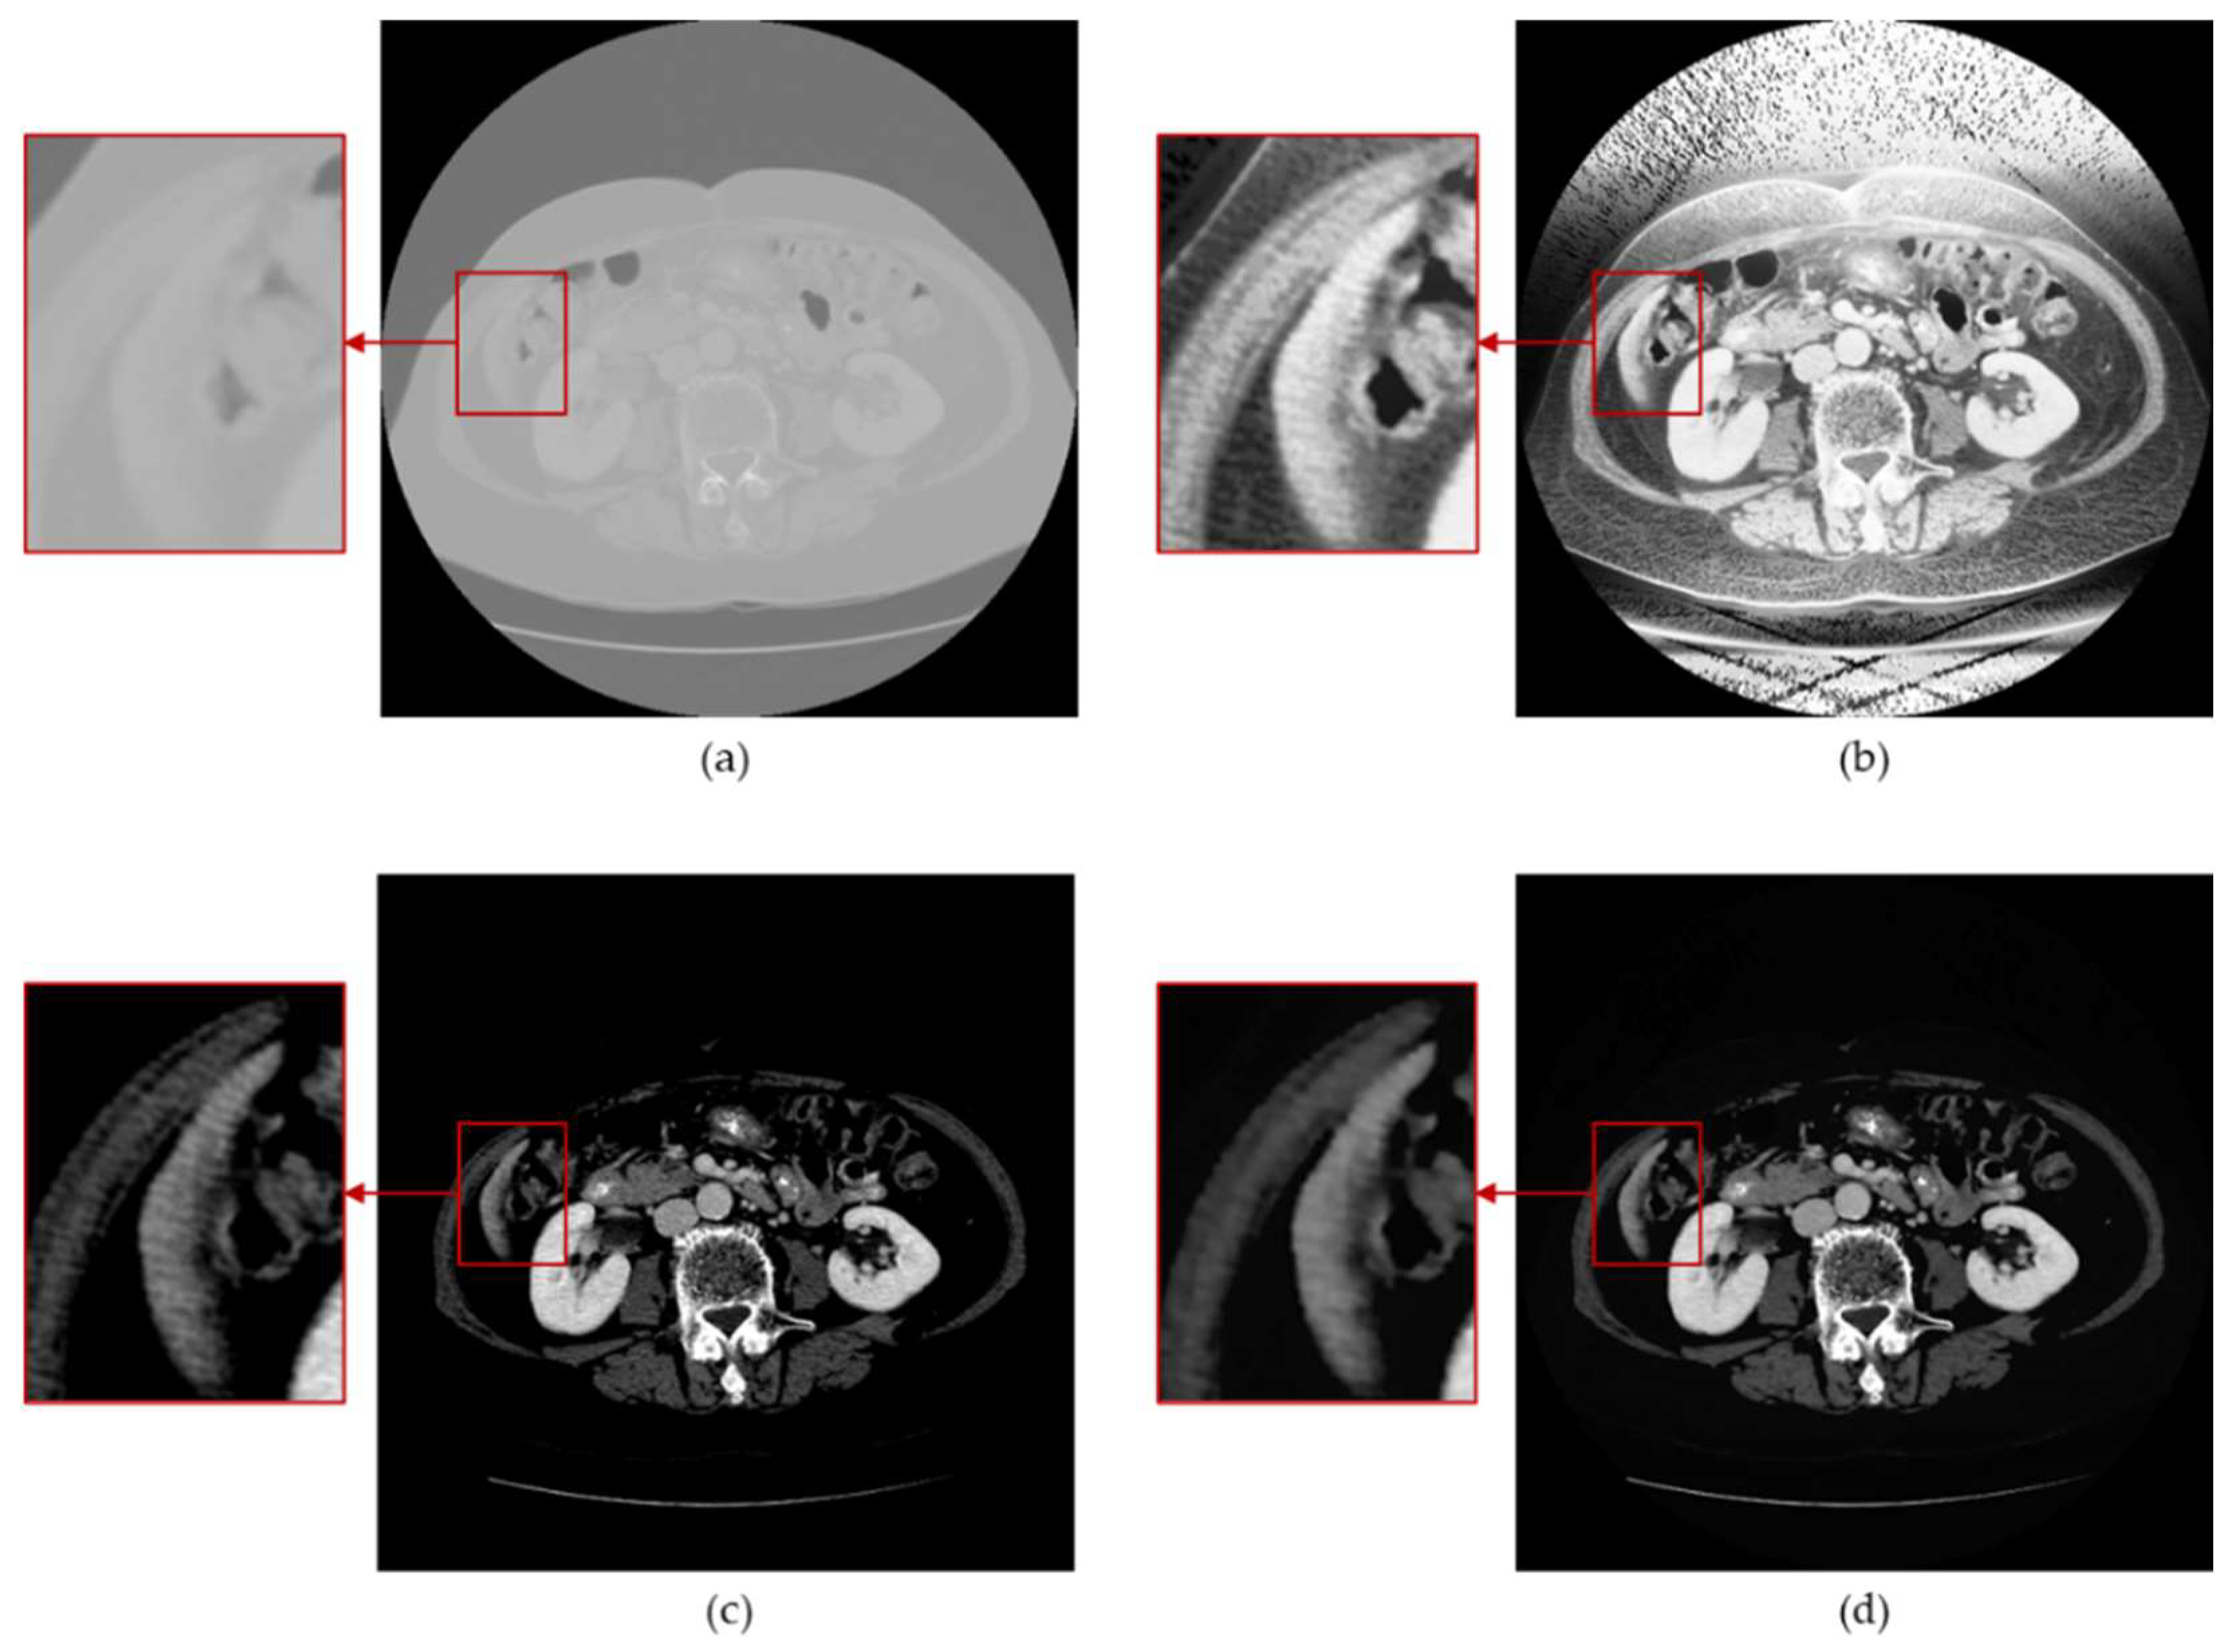

- Digital image enhancement strategies for medical image features: Medical images often contain a high level of noise and details hidden in low-intensity regions. To address this, anisotropic diffusion filters are used for denoising, and histogram equalization is employed to enhance the texture and details of medical images globally. Additionally, the fusion of window level and window width adjustment techniques specific to medical images is applied to target the regions of interest within the image. These strategies aim to achieve global enhancement of medical images while highlighting the desired targets.

3.1. Medical Image Enhancement Scheme—Procedure and Structure

3.3. Histogram Equalization

3.4. Window Adjustment